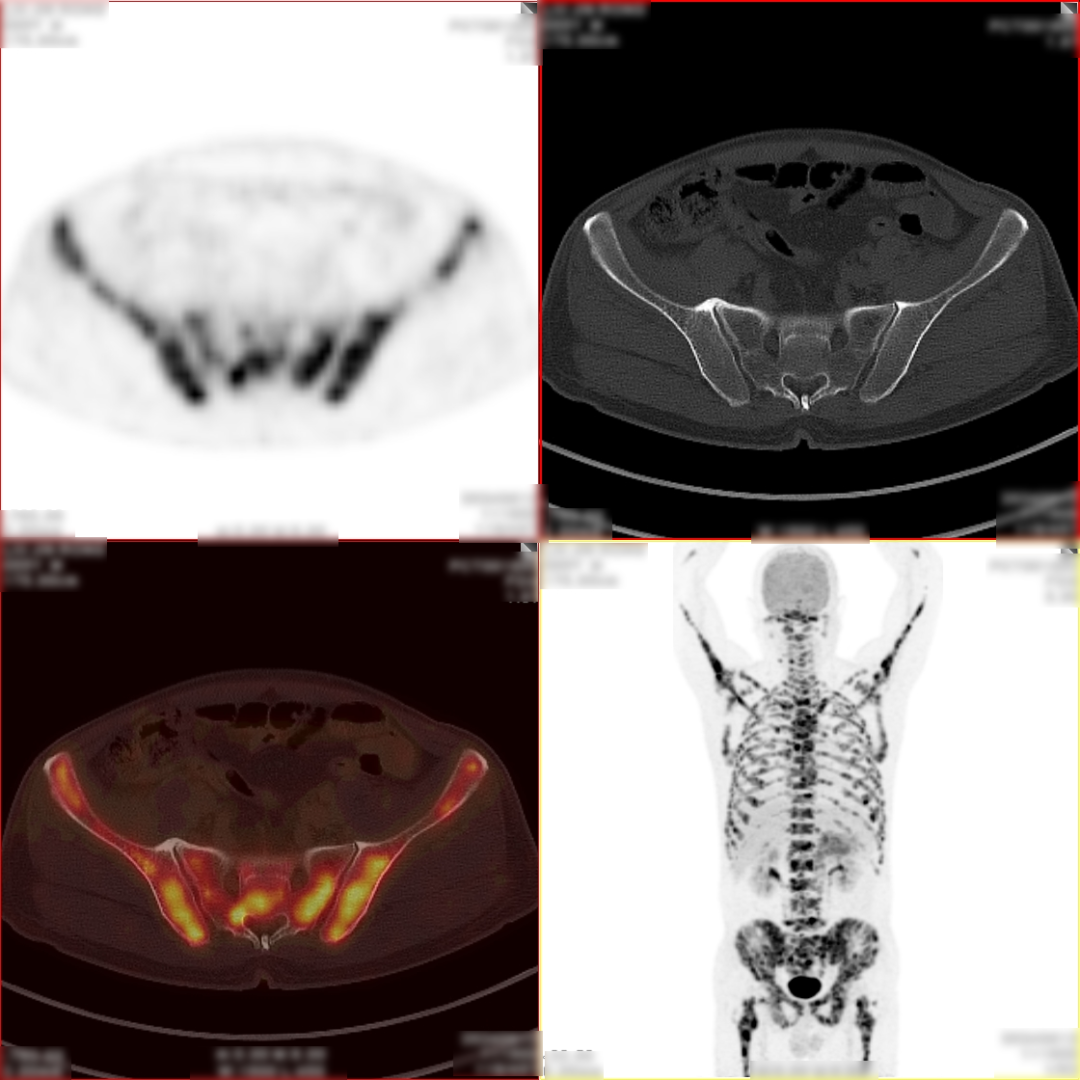

病史:男,55岁,腹痛伴乏力3天入院检查,MR:胰尾部肿物,考虑胰腺癌并多发淋巴结转移;超声胃镜下胰腺活检未见癌细胞,为了解全身状况申请PET检查。

PET/CT检查所见

空腹 6h 以上,静脉注射显像剂 18F-FDG,平静休息 60min 后行全身 PET 及 CT 断 层显像,解剖与功能图像行多层面、多幅显示,影像清晰。

PET/CT诊断意见:

3、双侧尺骨近端、双侧肱骨、右侧颞骨、枕骨、蝶骨、双侧下颌骨头、双侧锁骨、双侧肩胛骨、胸骨、脊柱各椎体、双侧各肋骨、骨盆诸组成骨、右侧股骨头、双侧股骨颈及股骨干广泛骨转移灶,其中左侧第 2、4 前肋、右侧第 4、7 侧肋病理性骨折。